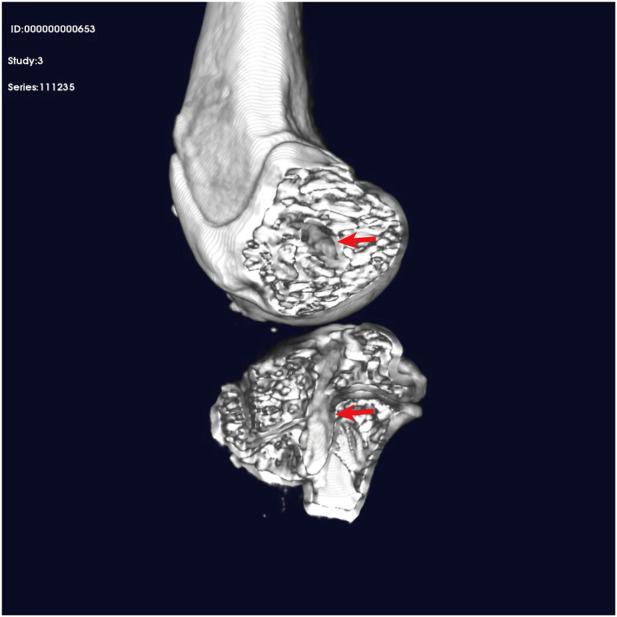

This study included 99 patients with ACL injuries who underwent all-inside arthroscopic ACL reconstruction using either the LARS internal brace ligament combined with hamstring tendon (augmentation group, n = 48) or hamstring tendon alone (hamstring group, n = 51). Postoperative follow-up was conducted using Lysholm, International Knee Documentation Committee (IKDC), Tegner, KOS-ADLS, and ACL-RSI scores to evaluate functional recovery of patients at 1, 3, and 6 months. If necessary, MRI findings obtained at postoperative 3 months were also analyzed to evaluate graft integration and healing dynamics. Tensile strength of the augmented graft was measured through tensile testing. Moreover, to evaluate the postoperative healing status of the augmented tendon, an ACL reconstruction model was established using New Zealand white rabbits. At 4 and 8 weeks postimplantation, rabbit knees were harvested, decalcified, embedded in paraffin, and stained to evaluate new tissue formation. All statistical analyses were conducted using the GraphPad Prism and SPSS software, with appropriate statistical tests applied for comparison between groups.

At 1-month postoperative follow-up, the LARS augmentation group demonstrated significantly higher Lysholm, IKDC, and KOS-ADLS scores than the hamstring group, with P < 0.01 for all comparisons. At 3-month postoperative follow-up, the augmentation group exhibited significantly higher Tegner, Lysholm, IKDC, and KOS-ADLS scores than the hamstring group, with P < 0.05 for all measurements. In the tensile testing, the tendons + LARS and LARS groups showed significantly higher maximum loads and lower elongation than the tendon group with P < 0.001 for maximum load and P < 0.05 for elongation. Examination of the histological sections at 4 and 8 weeks showed that the LARS ligament exhibited excellent biocompatibility, with abundant collagen fibers and neovascularization identified between its fibers.